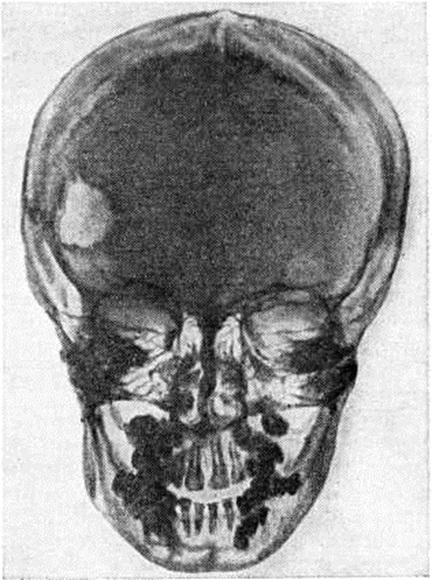

Рис. 2.

Рентгенограмма черепа при болезни Хенда — Шюллера — Крисчена: чёткий очерченный дефект костной ткани в лобной кости.

Рентгенологические картина характеризуется преимущественным поражением костей черепа (рисунок 2), таза, реже в процесс вовлекаются позвонки, ребра и длинные трубчатые кости (бедренные, плечевые, кости голени). В костях свода черепа образуются множественные дефекты неправильно округлой или овальной формы с чётко очерченными изъеденными контурами без признаков остеопороза и реактивных склеротических изменений по периферии. Размеры очагов варьируют, иногда очаги занимают обширные участки кости. Деструктивные процессы в области пирамиды, сосцевидного отростка и других отделов височной кости являются причиной поражения уха. Турецкое седло, как правило, не изменено. В ряде случаев выявляется небольшое его уплотнение. Из костей лицевого черепа изменения чаще обнаруживаются в челюстях, особенно в верхней. При поражении альвеолярных отростков наблюдается расширение зубных альвеол. В области таза очаги деструкции локализуются преимущественно в крыльях подвздошных костей. Поражение позвонков чаще бывает одиночным, встречается преимущественно в средней и нижней части грудного отдела позвоночника. Иногда развивается компрессия тел позвонков с образованием платибрахиспондилии (смотри полный свод знаний: Позвоночник) при сохранных межпозвоночных дисках. В редких случаях патологический перелом позвонка может быть первым клинические, признаком болезни. Трубчатые кости вздуваются изнутри, содержат множественные очаги деструкции различной величины, корковое (компактное) вещество истончено, секвестров не наблюдается. При субкортикальном расположении очагов могут возникнуть периоститы (смотри полный свод знаний).